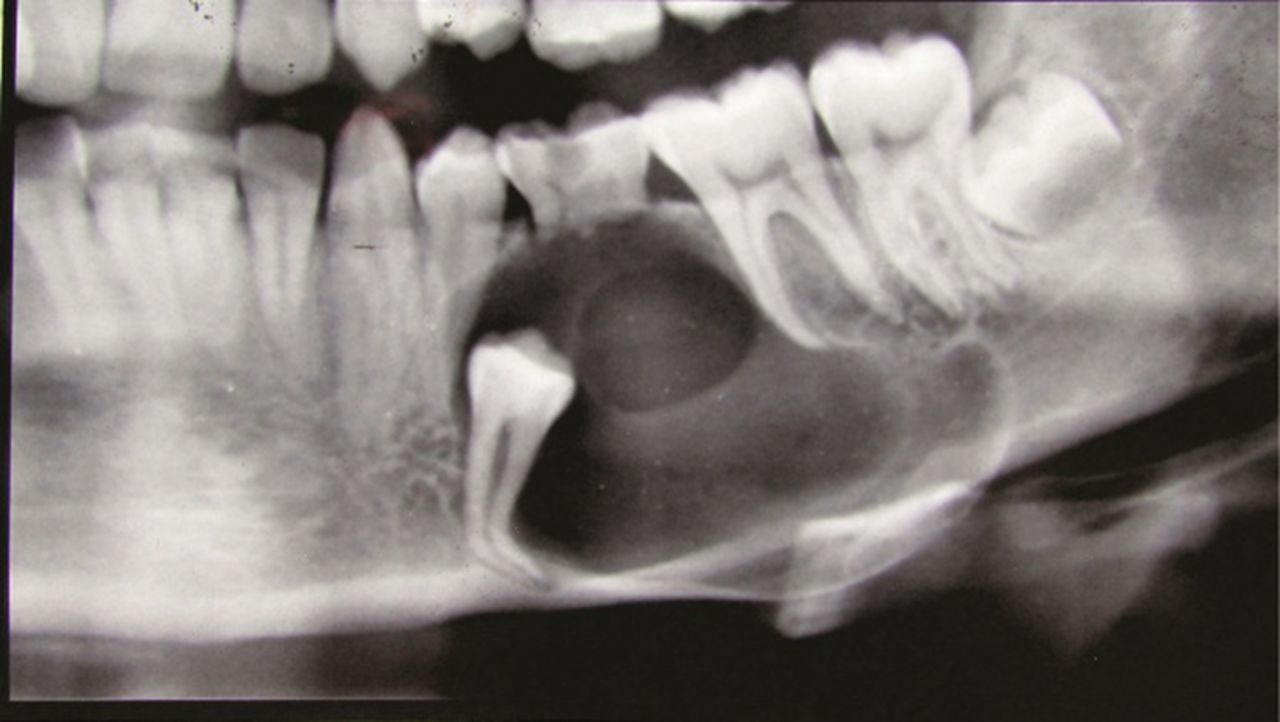

Dentigerous cysts are the second most common type of odontogenic cyst, which is a fluid-filled sac that develops in the jaw bone and soft tissue. They form over the top of an unerupted tooth, or partially erupted tooth, usually one of your molars or canines. While dentigerous cysts are benign, they can lead to complications, such as infection, if left untreated.

How is it diagnosed?

Small dentigerous cysts often go unnoticed until you have a dental X-ray. If your dentist notices an unusual spot on your dental X-ray, they may use a CT scan or MRI scan to make sure it’s not another type of cyst, such as a periapical cyst or an aneurysmal bone cyst.

In some cases, including when the cyst is larger, your dentist may be able to diagnose a dentigerous cyst just by looking at it.

Treating a dentigerous cyst depends on its size. If it’s small, your dentist might be able to surgically remove it along with the affected tooth. In other cases, they might use a technique called marsupialization.

Marsupialization involves cutting open the cyst so it can drain. Once the fluid has drained, stitches are added to the edges of the incision to keep it open, which prevents another cyst from growing there.